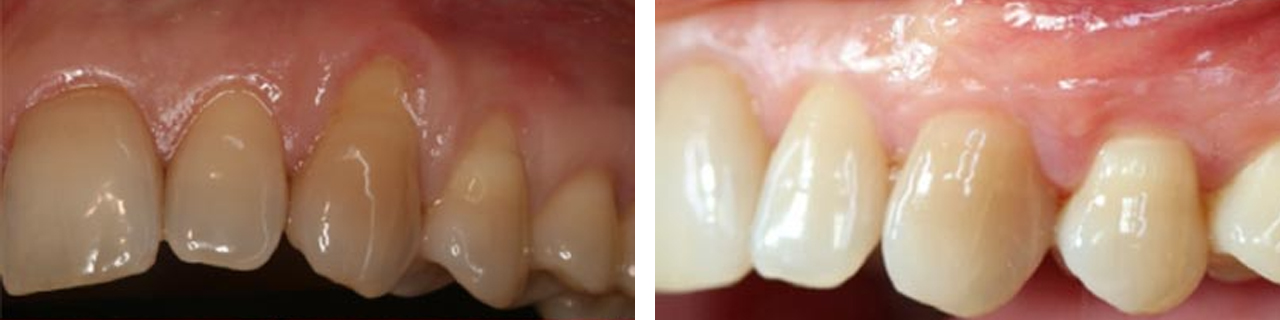

Cubrimiento de raíces expuestas.

Cubrimiento de raíces expuestas y aumento del grosor de la encía.